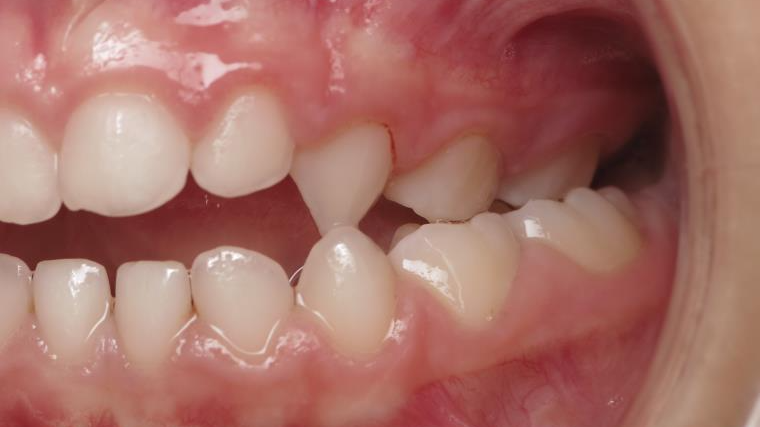

14 béance inversé gauche 5 ans

inversion postérieur coté droit et espace entre l'arcade du haut et du bas (béance)